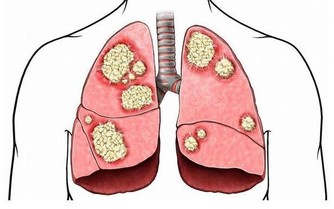

川嶋朗曾寫過《溫活》相關書籍,在書中它強調的是提升人體溫度,對保養身體有好處,因為在低溫的情況下,血液循環會變差,營養和血液以及氧氣供應就會不及時,免疫系統也會因此受到破壞,身體素質自然也就容易變差,可能會引起相關疾病。

另一方面,就是反應了人體內的陽氣不足,側面反應就是體內寒氣過剩,在寒氣較多的狀態下,人的體溫也就會自主調節,會顯得比較低。而寒氣變多,會影響氣血的運行,氣血很容易不足,氣血與陽氣都不充足,發生疾病的機率也就容易變大,免疫力和抵抗力就很難正常運作。